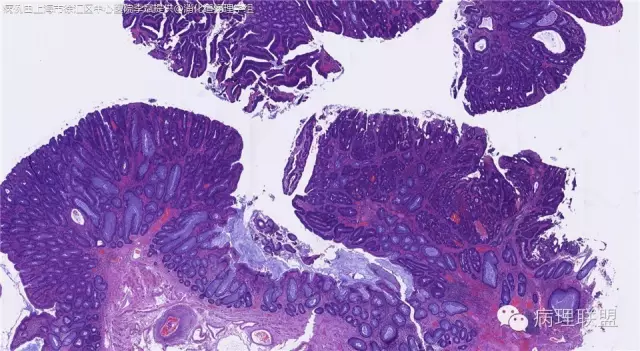

男,72岁,距肛门口30cm息肉。大体:灰白结节1.5*1*0.8cm拟发管状腺瘤并部分区高级别,请各位老师指导!(病例由上海市徐汇区中心医院 李斌 提供,致谢!)

这一例有两种不同看法,按WHO标准,为高级别,按实际工作,要发粘膜内癌。WHO第三版与第四版均提出,侵犯至粘膜下层才能诊断为癌,声称结直肠粘膜内没有淋巴管,发生转移的概率较小,但是粘膜内有血管,肿瘤侵出粘膜腺体基膜以外,就能侵犯血管,照样可以发生血道转移。文献报告与我们的工作实践,发现腺瘤、高级别(没有侵出基膜)的患者,同样有发生血道转移。因此,我们废弃了这一条WHO标准(不是所有的WHO标准都是一定要执行的)。只要异型增生腺体呈毛刺状、迷芽状侵出粘膜腺体基膜,位于粘膜肌层以内,就发粘膜内癌。

@李斌 结肠腺瘤这例我认为已经有黏膜下浸润了,因为有些腺体间的间质已经不是固有膜间质而是促结缔组织增生反应的间质了。但即使有浸润癌,如果息肉完整摘除、癌成分分化好、没有脉管瘤栓、浸润癌距切缘大于1mm(日本标准还要看浸润癌超出黏膜肌深度和肿瘤出芽情况),也不需要进一步治疗。所以,对于这类可能存在争议的病变,特别是息肉已经完整切除的病例,诊断的关注点就应该放在寻找需不需要进一步治疗的证据上了。@邓永键 2010版WHO在腺瘤部分的陈述中已经写出对于有局灶浸润性生长的病例也可以称黏膜内癌,他们在悄悄的让步。